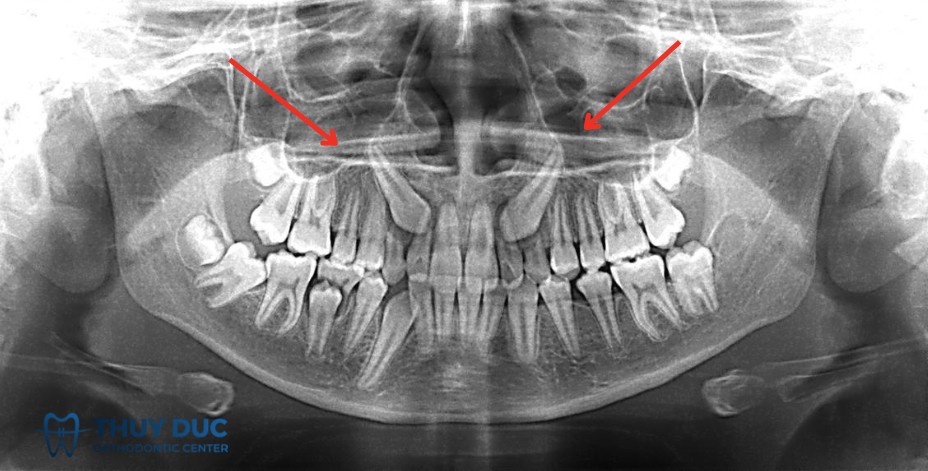

Vì vậy, phương pháp chẩn đoán chính xác nhất là chụp X-quang (thường là phim panorama hoặc phim cận chóp). Trên thực tế, rất nhiều bệnh nhân chỉ phát hiện mình có răng mọc ngầm khi đi khám và chụp phim để điều trị một vấn đề khác, ví dụ sâu răng, viêm nha chu hoặc chuẩn bị niềng răng.

2.1 Răng khôn mọc ngầm

Răng khôn là răng mọc cuối cùng trên cung hàm, thường xuất hiện ở độ tuổi 18-25. Do mọc muộn, cung hàm thường không còn đủ khoảng trống, khiến răng khôn dễ bị kẹt trong xương hoặc mọc lệch. Răng khôn mọc ngầm có thể gây đau, viêm, sâu răng lân cận vàđôi khi hình thành nang xương. Đây là loại răng mọc ngầm phổ biến nhất.